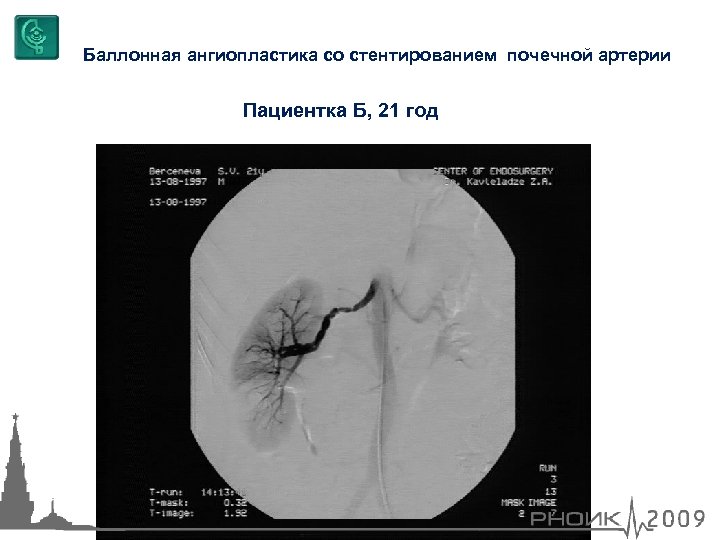

Баллонная ангиопластика со стентированием почечной артерии Пациентка Б, 21 год

Баллонная ангиопластика со стентированием почечной артерии Пациентка Б, 21 год

Балонная ангиопластика со стентированием почечной артерии Пациентка Б, 21 год

Балонная ангиопластика со стентированием почечной артерии Пациентка Б, 21 год